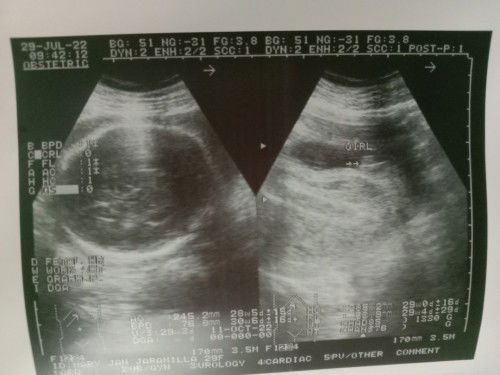

Confirm baby girl na ba ?

Hi mga momsh, 😊. Sa tingin nyu po ba baby girl na talaga si baby ? 🥰♥️. Excited po kasi ako eh. Hehhee. Kasi sa family ng husband ko ngayon lang magkaka girl na baby kaya excited sila, sa lahi kasi nila puro boy ang mga apo , kaya excited sila na magkakaroon na ng baby girl 😊♥️. Sana po mapansin 😊. Thank youuu ♥️